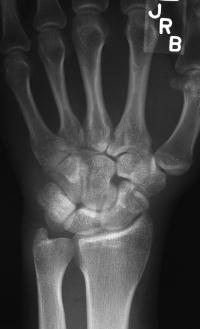

Clinical Example: Scaphoid Tubercle Fracture

scaphoid tubercle fracture